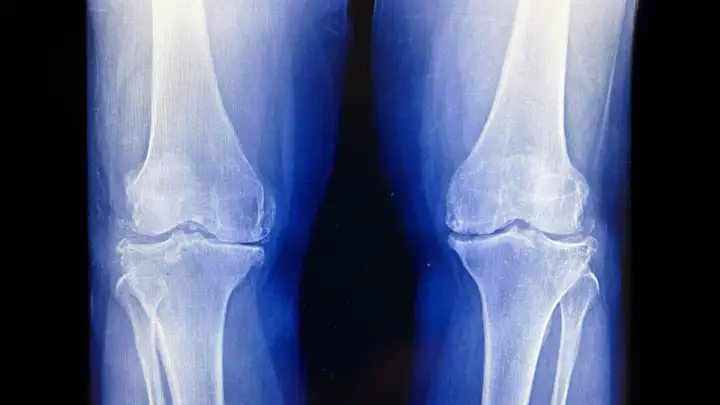

Результаты нового клинического исследования, проведенного Медицинским колледжем Сеульского национального университета (Южная Корея), показали, что однократный курс низкодозной лучевой терапии может облегчить боль и улучшить функцию сустава у пациентов. В исследовании приняли участие 114 пациентов, у которых был диагностирован умеренный остеоартрит коленного сустава, выявленный на рентгеновских снимках.

Радиация успешно притормозила развитие артрита в коленях. Радиация успешно притормозила развитие артрита в коленях.© Commons/NP2025 CC BY-SA 4.0